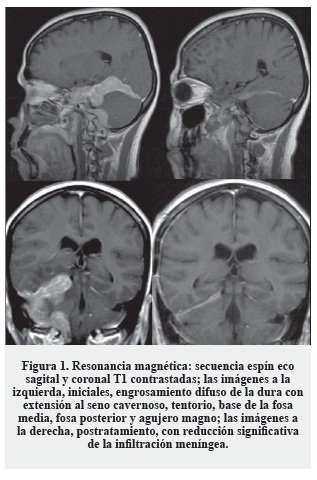

Mujer de 47 años con cuadro de veinte días de evolución en disminución de la fuerza en el miembro inferior derecho y cefalea; antecedentes sin importancia. Se realizó TC de cráneo y se diagnosticó un hematoma subdural agudo frontotemporal izquierdo, fue llevada a cirugía. El cuadro persistió sin mejoría clínica y se efectuó IRM, que se interpretó como hematoma compresivo, por lo cual fue reintervenida, resecando parcialmente una lesión extraaxial sólida sin hematoma; la patología inicial fue reportada como meningioma vs. lesión plasmocitaria y la segunda como astrocitoma grado III. Remitida al Instituto Nacional de Cancerología para una segunda opinión, se le realizó nuevo TC y se hizo revisión de la patología ("Imágenes", Figura 3).

El estudio histopatológico fue de difícil clasificación, se observaba proliferación de células pequeñas con moderado citoplasma ("Patología", Figura 6A) formando sabanas con manguitos perivasculares y plasmocitos. Los hallazgos plantean inicialmente linfoma vs. tumor glial de alto grado. Se llevó a cabo estudio de inmunohistoquímica que descartó la naturaleza glial de la lesión, dada la negatividad para la proteína ácida fibrilar glial (GFAP), y confirmó la de un linfoma por la positividad para CD20 con coexpresión de Bcl-2 ("Patología", Figura 6B) y Ki-67 bajo. La lesión se clasificó entonces como linfoma B no Hodgkin de célula pequeña de tipo linfoma marginal (Tabla 1).